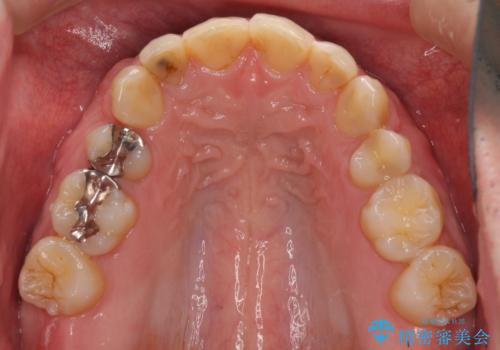

- 前歯の見た目を主訴にご来院された患者様です。虫歯治療を複数回繰り返して、前歯のつめものがつぎはぎになっていました。

当初は1番目立つ1本だけをご希望でしたが、相談の結果、隣の歯(神経が抜いてあり金属が入っている歯)と2本同時に製作することになりました。

患者様は前歯の見た目の改善を主訴にご来院されました。上の前歯6本とも古いつめものがつぎはぎになっていましたが、まずは1番目立つところを治すことをご希望でした。相談の結果、今回は2本できれいになるように工夫しました。